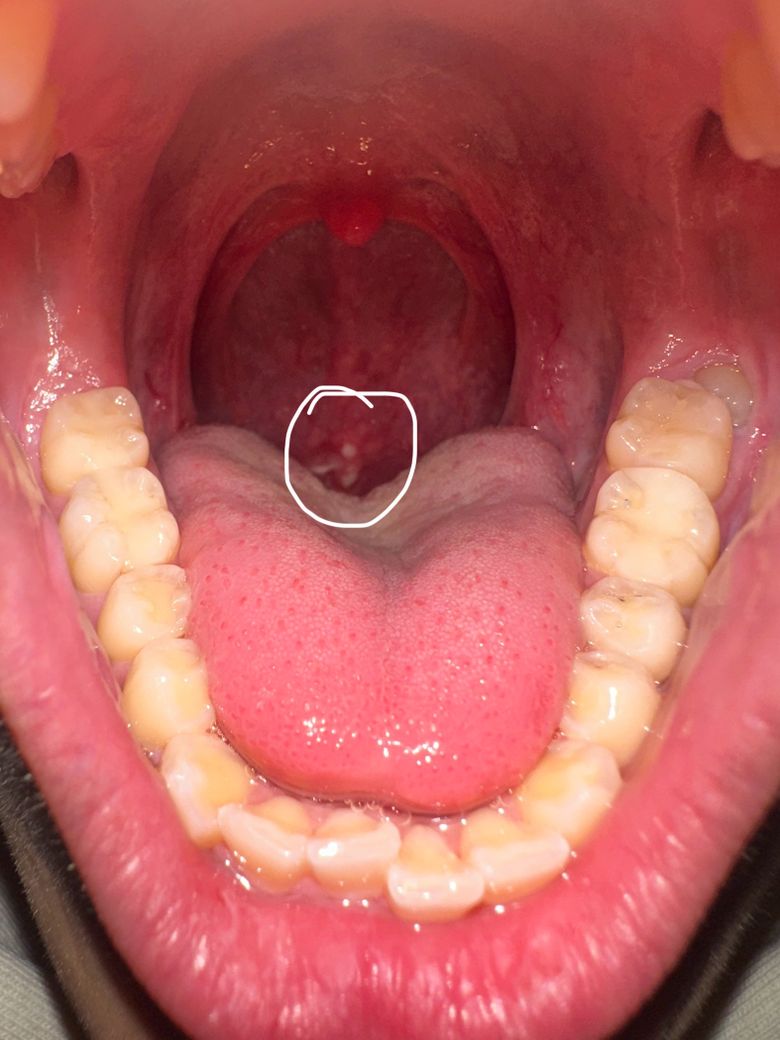

목에 하얀색 덮인 이거 뭔지 알려주세요 ㅠㅠ

목에 이거 뭔지 좀 알려주세요 ㅠㅠ 제가 목이 막히는 느낌이 들고 이물감 있고 따갑고 아팠는데 약 먹니니까 조금은 괜찮아졌습니다.. 근데 지난주부터 보니까 입 안쪽에 처음에는 구내염처럼 보였는데 오늘 보니까 갑자기 저렇게 하얀색으로 뭐가 덮어져 있습니다.. 저게 혹시 뭔지 알수있을까여?? ㅠㅠ 낼 내과는 가보려고 하는데 사진 있습니다 제가 어제까지 먹었던 약들입니더

여러 가지 원인에 의해 발생할 수 있습니다. 목젖 부위는 점막이 있기 때문에 저런 돌출물이 나타날 수 있으며, 그 원인으로는 구강 감염이나 구내염, 편도선 염증, 혹은 혀나 입안의 자극으로 인한 문제일 수 있습니다.

목젖에 나타나는 하얀 돌기나 좁쌀 같은 것은 편도선에 염증이 생기거나 편도선 결석(편도선에 낀 음식물 찌꺼기나 세균 덩어리로 인해 하얗게 보이는 것)일 가능성도 있습니다. 또한 구내염이나 감기 초기 증상에서도 목젖 주변에 자극을 주거나 염증을 일으킬 수 있구요